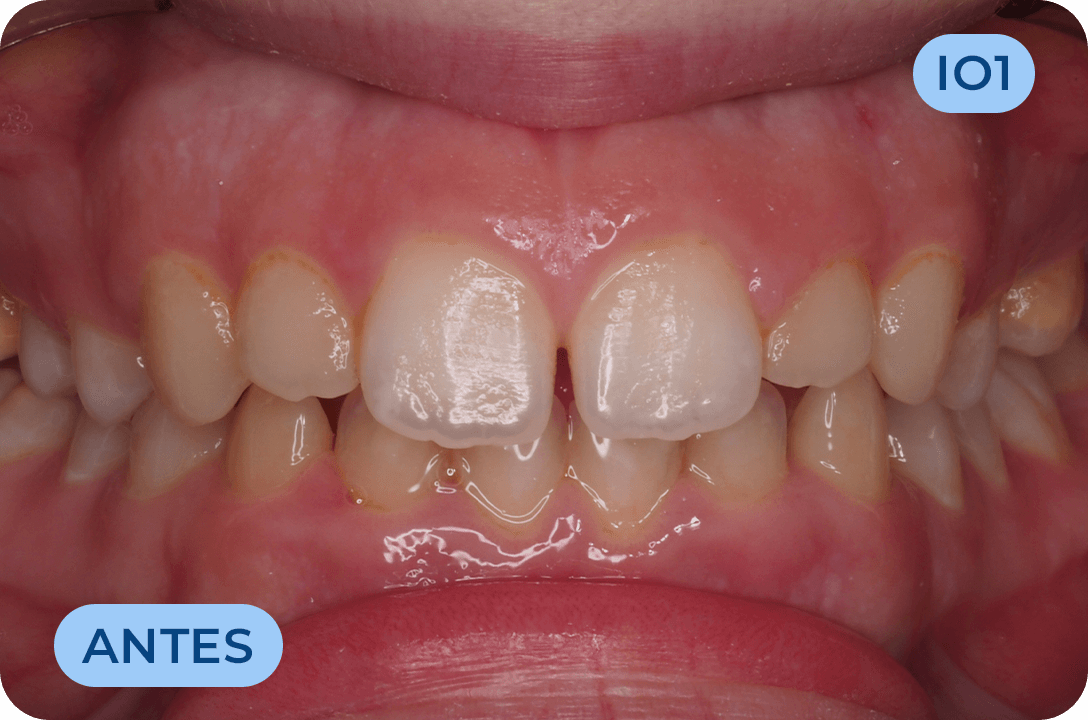

Ortodontia

É a especialidade da Medicina Dentária que se debruça sobre o estudo e correção das más posições dentárias e dos maxilares. Atualmente é possível tratar pacientes de todas as idades, no entanto a 1ª consulta deve ser realizada ainda na infância para intercetar eventuais problemas de desenvolvimento esquelético e funcional.